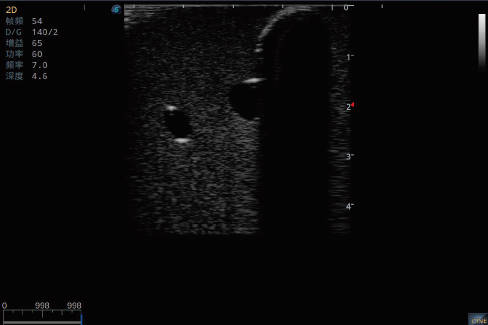

深静脉置管模型

产品型号 NO.TY1510.2

产品尺寸(mm) 700×500×160